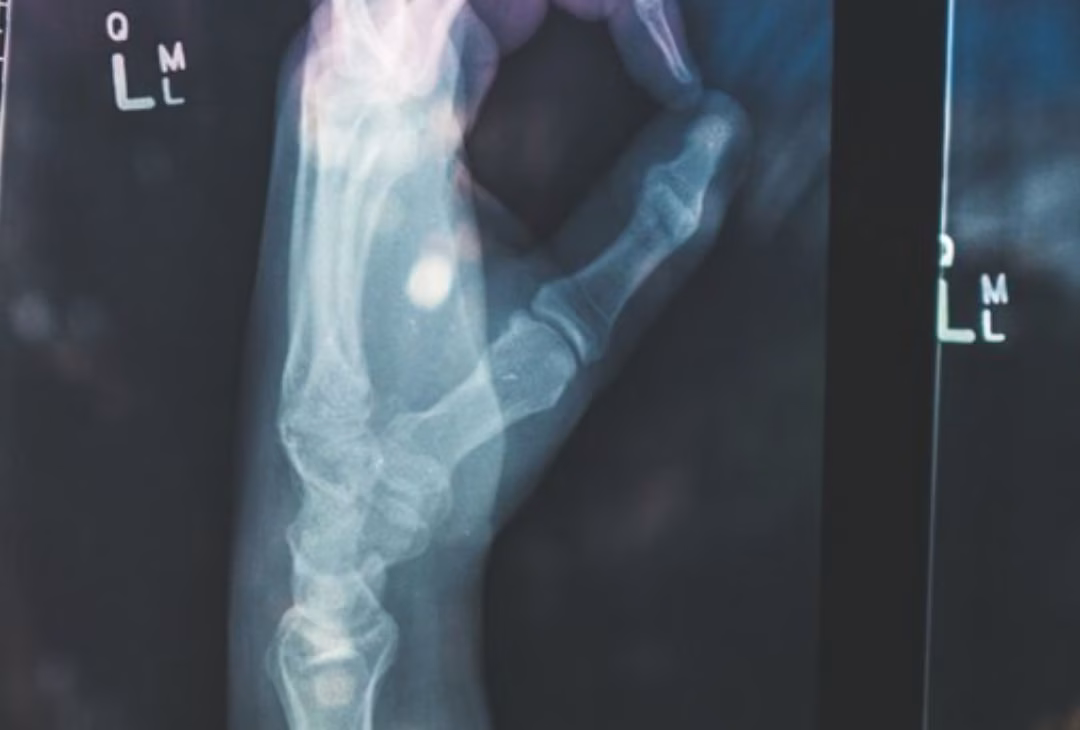

A gel is applied to the area of the body that requires the scan and the end of the handheld scanner. The gel allows the sound waves to transmit between the two better, giving a clearer vision on the screen. You will be able to see the needle entering the space and the fluid leaving the needle into the area of the body where it is targeted. See below for examples of previous Ultrasound scans.

Michael Has Extensive Experience using advanced imaging such as MRI, Xray and CT to assist with diagnosis and treatment planning. If required and consented you may be referred for additional investigations.